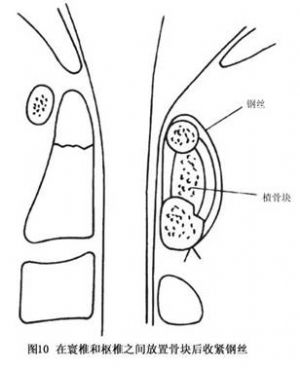

14.3.3 Gallie手术

Gallie手术多用于寰枢关节脱位明显者,如图8~10所示。先切取植骨块将其修成相应大小及所需的形状,之后将钢丝穿过寰椎后弓,再穿过枢椎两侧后弓下方收紧钢丝,使骨块嵌于颈1、2棘突之间即达复位及融合目的。本法的骨融合成功率较前者低,但对转颈活动影响较少。